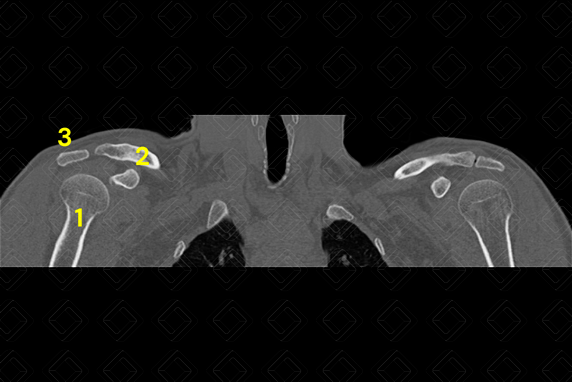

Texto alternativo para a imagem Figura 2. Tomografia computadorizada dos ombros - plano coronal.

Créditos: Athena Hub/Medical Harbour

Legenda: 1 = úmero; 2 = clavícula; 3 = acrômio; e 4 = escápula.